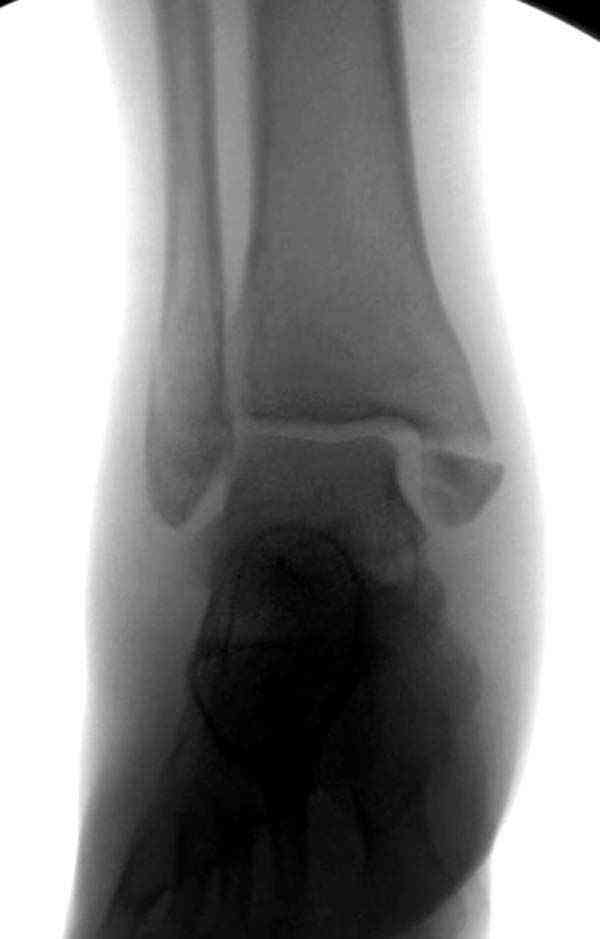

Достаточно быстрое восстановление функции.В октябре 2009г-почувствовала боль,в области рубца над гайкой открылся свищ.На Р-граммах-консолидация переломов и смещение гайки по стяжке.10.11.2009г-конструкции удалены,санация,заживление ран.В настоящее время пациентку ничего не беспокоит.На операции-раскручивание гайки-болталась на конце стяжки.Вопросы:какой механизм раскручивания и что я неправильно сделал?Свои версии:1)в области синдесмоза успела образоваться рубцовая ткань,которая при движении в суставе"пружинила",поскольку голеностопный сустав является спиральным, то и биомеханика подобна кривошипному механизму.2)Реконструктивная пластина не "реконструировалась" по форме лодыжки.Наложил,как есть.То есть подпружинивала сама пластина.Ну,это мои догадки.Что нужно,чтобы избегать впредь таких,пусть и не "страшных"осложнений:Рассверливать через лодыжку область синдесмоза?Ставить шайбу-гровер?Тщательно моделировать пластину?Прилагаю сравнительные снимки-сразу после операции и перед удалением конструкции.

Визуально никаких вопросов по репозиции не было.Да и на основании чего сомнения,что наружная лодыжка не полностью репонирована или прорезалась проволка ???Я не вижу...Снимок после репозиции справа.

Нет первичных снимков, перелом очень низкий и под большим сомнением диагноз разрыва синдесмоза. Медиальная сторона отрепонирована на "хорошо" и, по-видимому, прорезание проволоки произошло во время операции. Без снимков трудно судить о высоте малоберцовой, а лодыжка находится в варусе. Лагирование получилось, но возле тонких шурупов передне-задний шуруп выглядит немного тяжеловато.